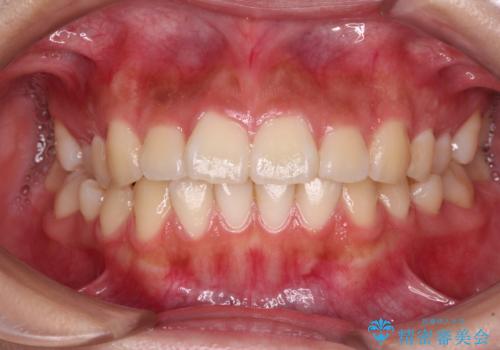

【ワイヤー矯正】八重歯 歯のでこぼこを治したい!